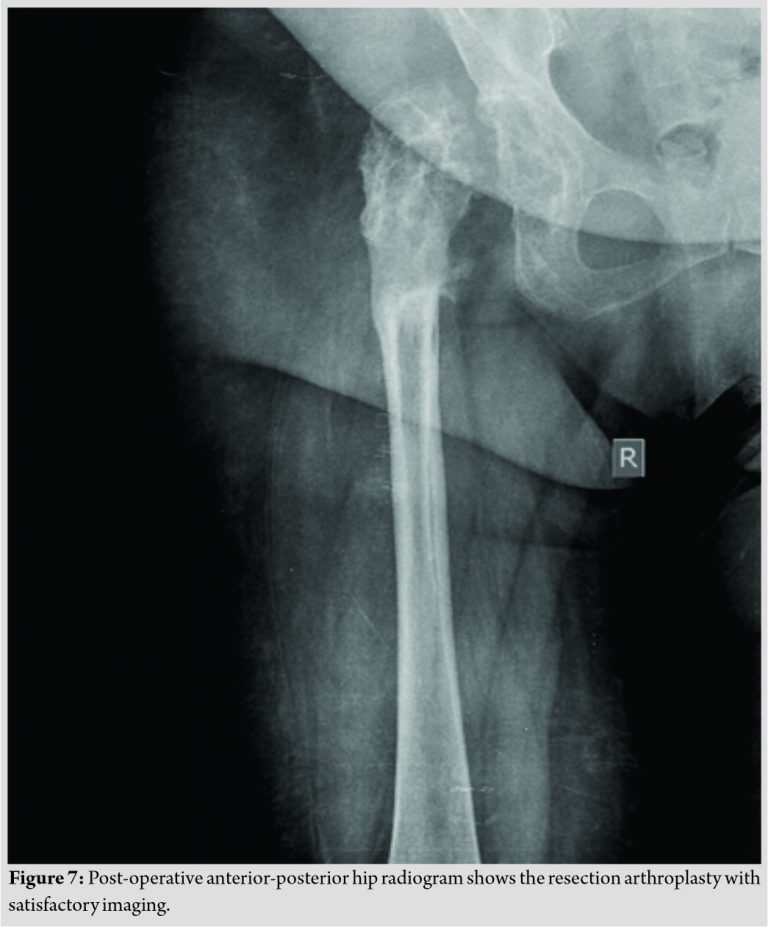

The wounds healed uneventfully. No cement spacer was placed, due to our patient’s refusal for revision THA surgery. The cultures of the retrieved specimens revealed a polymicrobial infection of Methicillin-resistant Staphylococcus aureus and proteus mirabilis, while biopsy revealed tissue infiltration of polymorphonuclear leukocytes and macrophage cells, due to both infection and adverse reaction to metal debris (ARMD). The histology of the thigh scar was negative for malignancy. We administrated 6 weeks of intravenous vancomycin and sulfamethoxazole plus trimethoprim followed by 6 weeks’ oral administration of linezolid plus trimethoprim and sulfamethoxazole. The final radiographic result was a resection arthroplasty (Fig. 7).

Fortunately, our patient was able to partially bear weight, with the aid of crutches, 1 month after surgery. The CRP and ESR returned to the normal levels, and our patient was discharged on day 51 after admission. Our patient had followed up, at 3 and 12 months postoperatively, with negative inflammation markers, no sinus formation, and satisfactory clinical and radiographic evaluation (Fig. 7).